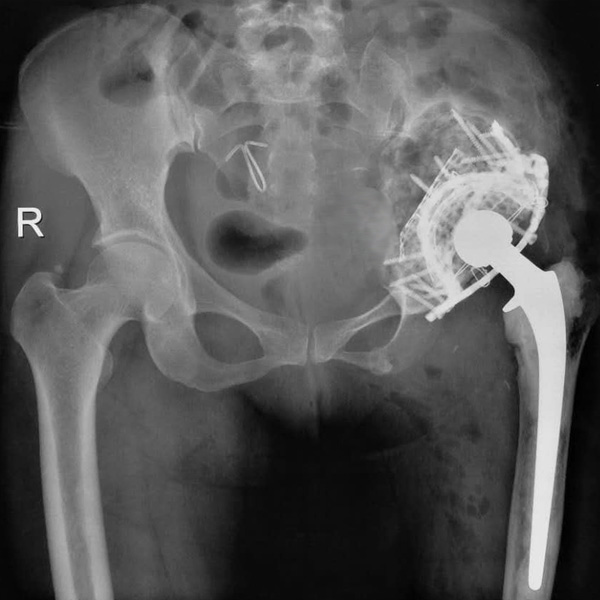

髖關節(jié)翻修

患者蘇某,女性,11年前因“左髖關節(jié)屈曲攣縮畸形”行左側人工全髖關節(jié)置換,近來感覺左髖關節(jié)疼痛,不敢行走,經(jīng)“攜生醫(yī)療平臺”就診于哈......